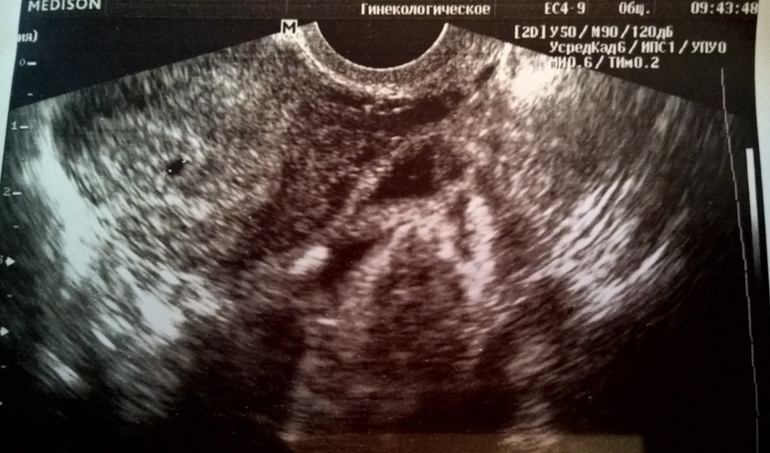

У нас все хорошо, срок ещё слишком маленький, поэтому эмбриончика ещё не видно, но беременность маточная, видно плодное яйцо (3,6 мм). Прописали дюфастон по 1 таблетке в день. Через 2 недели пойду на повторное УЗИ, чтобы убедиться, что все хорошо. А пока любуюсь на маленькую точечку на снимке с УЗИ

Спасибо! У меня 15 декабря, так что мы на одном сроке )) Делали вагинальный датчиком, но увидели только плодное яйцо, эмбриона ещё разглядеть нельзя. Так что не волнуйтесь, ещё просто очень рано )) мне вот сказали, что у них даже программа не рассчитана на такой маленький срок - не может рассчитать недельки по размерам плодного яйца

По моим расчетам почти 5 недель (акушерских), точно смогут сказать только на следующем узи. По крайней мере я на это надеюсь ))